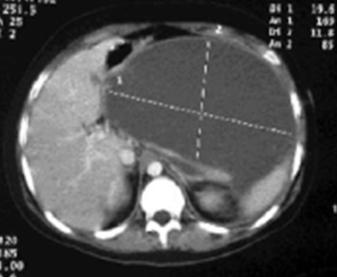

Tomografía: determina la localización

♦ La mayoría de los gastrinomas se encuentran en un área llamada triángulo del gastrinoma. (Ver Figura 58)

♦ Duodeno (70% de los casos)

♦ Páncreas (25% de los casos) → típicamente la cabeza

♦ Ubicaciones ectópicas (5 a 15% de los casos): Hígado, ganglios linfáticos peri pancreáticos, ovarios

Figura 56. Prueba de secretina para gastrinoma. La hipersecreción marcada de gastrina ocurre después de la administración de secretina en un paciente con un gastrinoma (síndrome de Zollinger-Ellison) en comparación con la falta de respuesta en sujetos normales.

Figura 58. Triangulo del gastrinoma → El vértice superior está formado por la unión de los conductos biliar y cístico , el vértice medial por el cuello del páncreas y el vértice inferior por la tercera porción del duodeno.